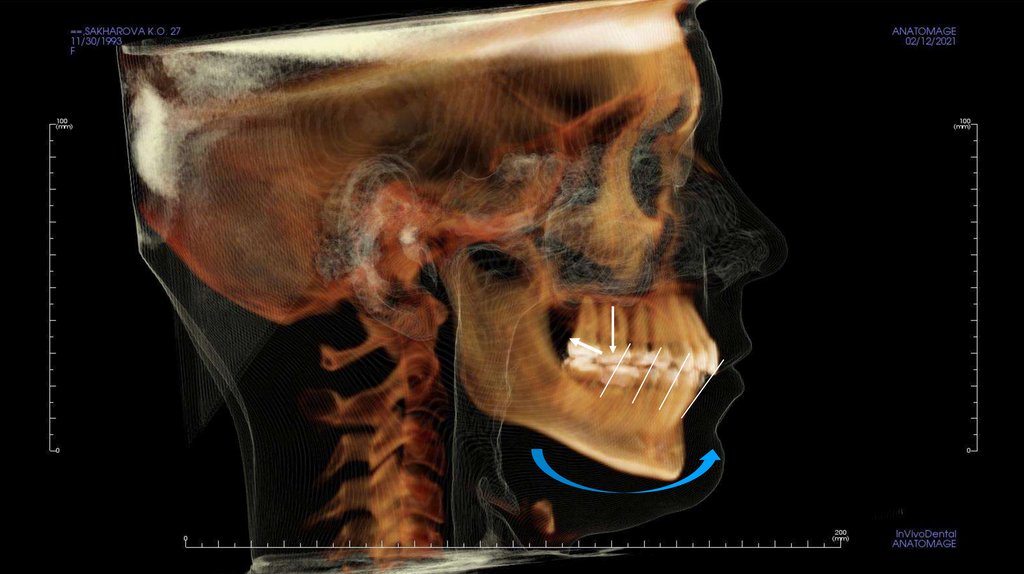

По рассчетам снимков:

• Ретрузия резцов верхней челюсти

• Компрессия головок суставов, особенно правого( началось

ремоделирование)

• Костная ассиметрия(10 мм)

• 2 класс

• 25, 46 зуб – нуждается в санации

• Требуется профессиональняа гигиена полости рта

• Клиновидные дефекты 43, 44

• 18, 28, 38, 48 отсутствуют.